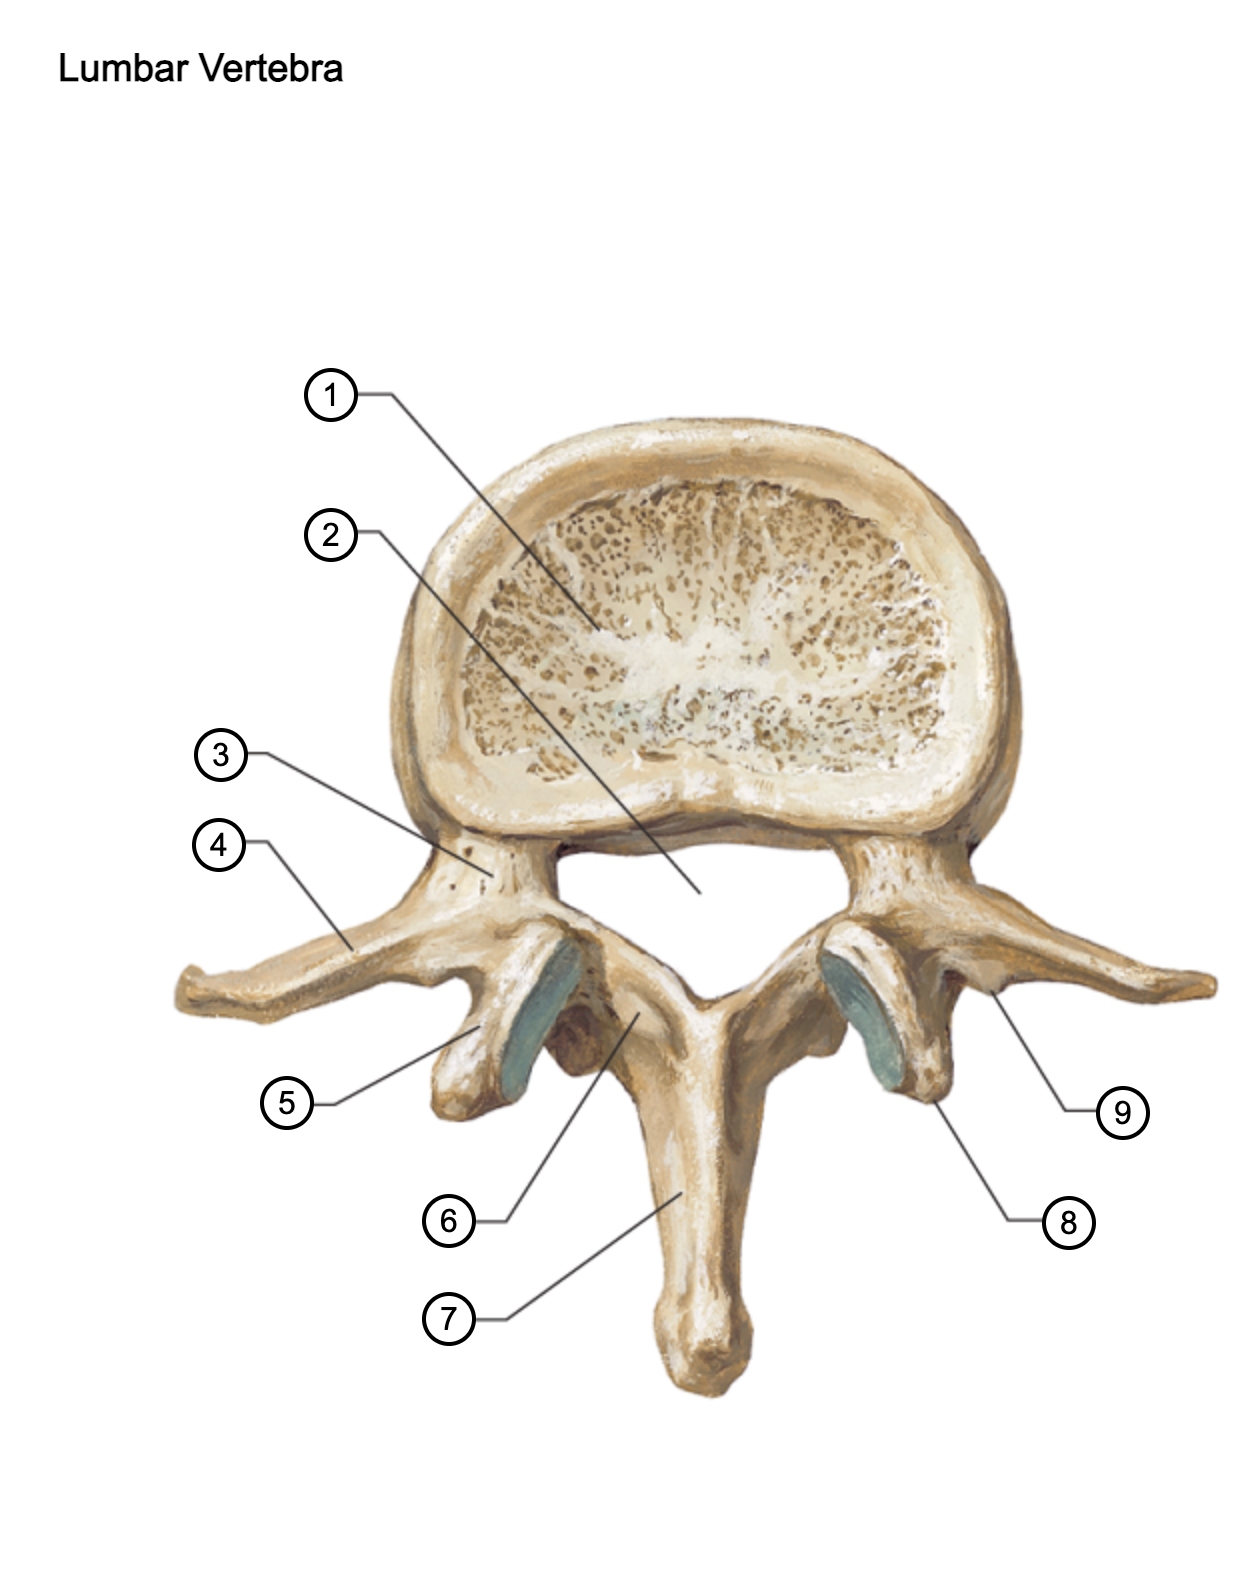

1

vertebral body

2

vertebral foramen

3

pedicle

4

transverse process

5

superior articular process

6

lamina

7

spinous process

8

mammillary process

9

accessory process